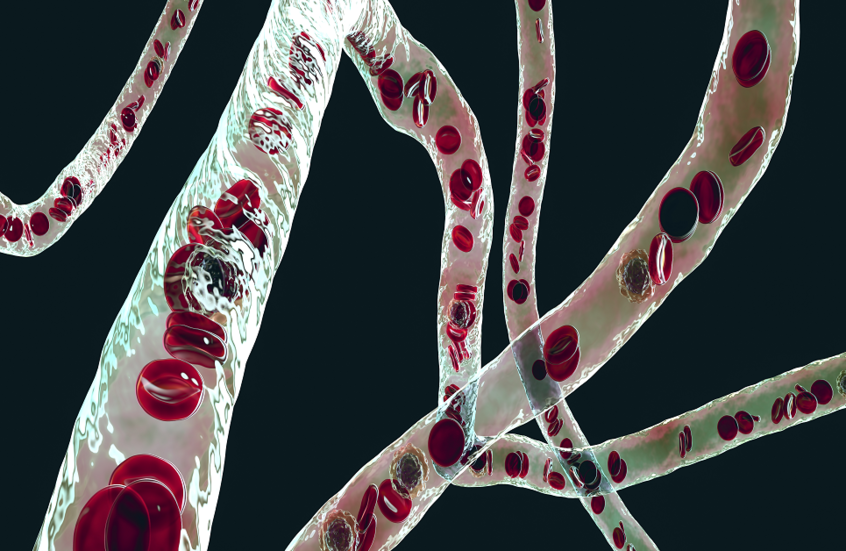

عملية زرع مع صمام خنزير قد تجنب مرضى القلب الجراحة العامة!

يمكن تجنيب المرضى الذين يعانون من حالة قلبية منهكة عملية جراحية كبيرة عن طريق زرع صمام إلكتروني.

وصمم الجهاز الصغير، الذي يمكن تركيبه في أقل من ساعة باستخدام مخدر موضعي، لعلاج قصور الأبهر، وهي حالة تؤدي إلى تجويع الدم المؤكسج في الجسم وتترك المرضى مرهقين.

وتحدث المشكلة عندما يتضرر الصمام الموجود عند مخرج القلب، الصمام الأبهري، ويفشل في الإغلاق التام. وهذا يسمح للدم بالتسرب للخلف إلى القلب ويؤثر على قدرته على الضخ بكفاءة. وهو الأكثر شيوعا عند المرضى الأكبر سنا والذين يعانون من ارتفاع ضغط الدم. وقد يكون الضرر أيضا بسبب العدوى.

وتتطلب الحالة جراحة القلب المفتوح، والتي تتضمن فتح صدر المريض، ووضع قلبه على آلة الالتفاف واستبدال الصمام.

ومع ذلك، يُترك العديد من المرضى أضعف من أن يتحملوا هذه الجراحة الكبرى. بالإضافة إلى ذلك، لم يكن هناك حتى الآن زرع صمام مصمم خصيصا لقصور الأبهر - يستخدم الجراحون غرسات مصممة لعلاج أشكال أخرى من أمراض الصمام.

تطوير جهاز قابل للزرع يذوب في الجسم عند انتهاء مهمته قادر على تخفيف الألم دون أدوية

ويمكن تركيب غرسة JenaValve Trilogy الإلكترونية الجديدة، التي تحتوي على إطار معدني وصمام من خنزير، خلال إجراء طفيف التوغل يستغرق أقل من ساعة. وقال طبيب القلب أندرياس بومباخ، الذي قاد الفريق الرائد في الجهاز في مستشفى سانت بارثولوميو في لندن: "لم يكن هناك شيء مثل هذا من قبل".

وستحدث ثلاثية JenaValve فرقا كبيرا. وتم علاج أول بضع مئات من المرضى الآن وكان هناك ما يقرب من 100% معدل النجاح.

وأثناء عملية زرع ثلاثية JenaValve، يتم إجراء شق صغير في الشريان الفخذي في الفخذ - يتم استخدام مخدر لتخدير المنطقة ولكن المرضى مستيقظون على نطاق واسع.

ثم يتم إدخال أنبوب دقيق ومرن يسمى القسطرة في الشريان ويتم تمريره عبر الجسم إلى القلب، باستخدام جهاز الأشعة السينية لمعرفة ما يقومون به في الوقت الفعلي. ويوضع JenaValve، المصنوع من إطار معدني على شكل أنبوب قابل للطي، في مكانه عبر القسطرة. وفي البداية يتم طيها، ولكن بمجرد أن يؤكد الجراح أنها في المكان المناسب، يتم فتحها.

وجرى توسيع الصمام بالكامل، ويبلغ قطره حوالي بوصة واحدة، ولكن يمكن تعديل الحجم في الموقع للتأكد من أنه مناسب تماما. وقال البروفيسور بومباخ إن ثلاث أرجل صغيرة - تشبه إلى حد ما الأرجل الموجودة على وحدة الهبوط على سطح القمر - تثبتها في موضعها فوق الصمام الأورطي الطبيعي، وتبدأ في العمل على الفور.

ثم يتم إزالة القسطرة وخياطة الشق والسماح للمرضى بالعودة إلى المنزل بعد يوم أو يومين.

المصدر: ديلي ميل